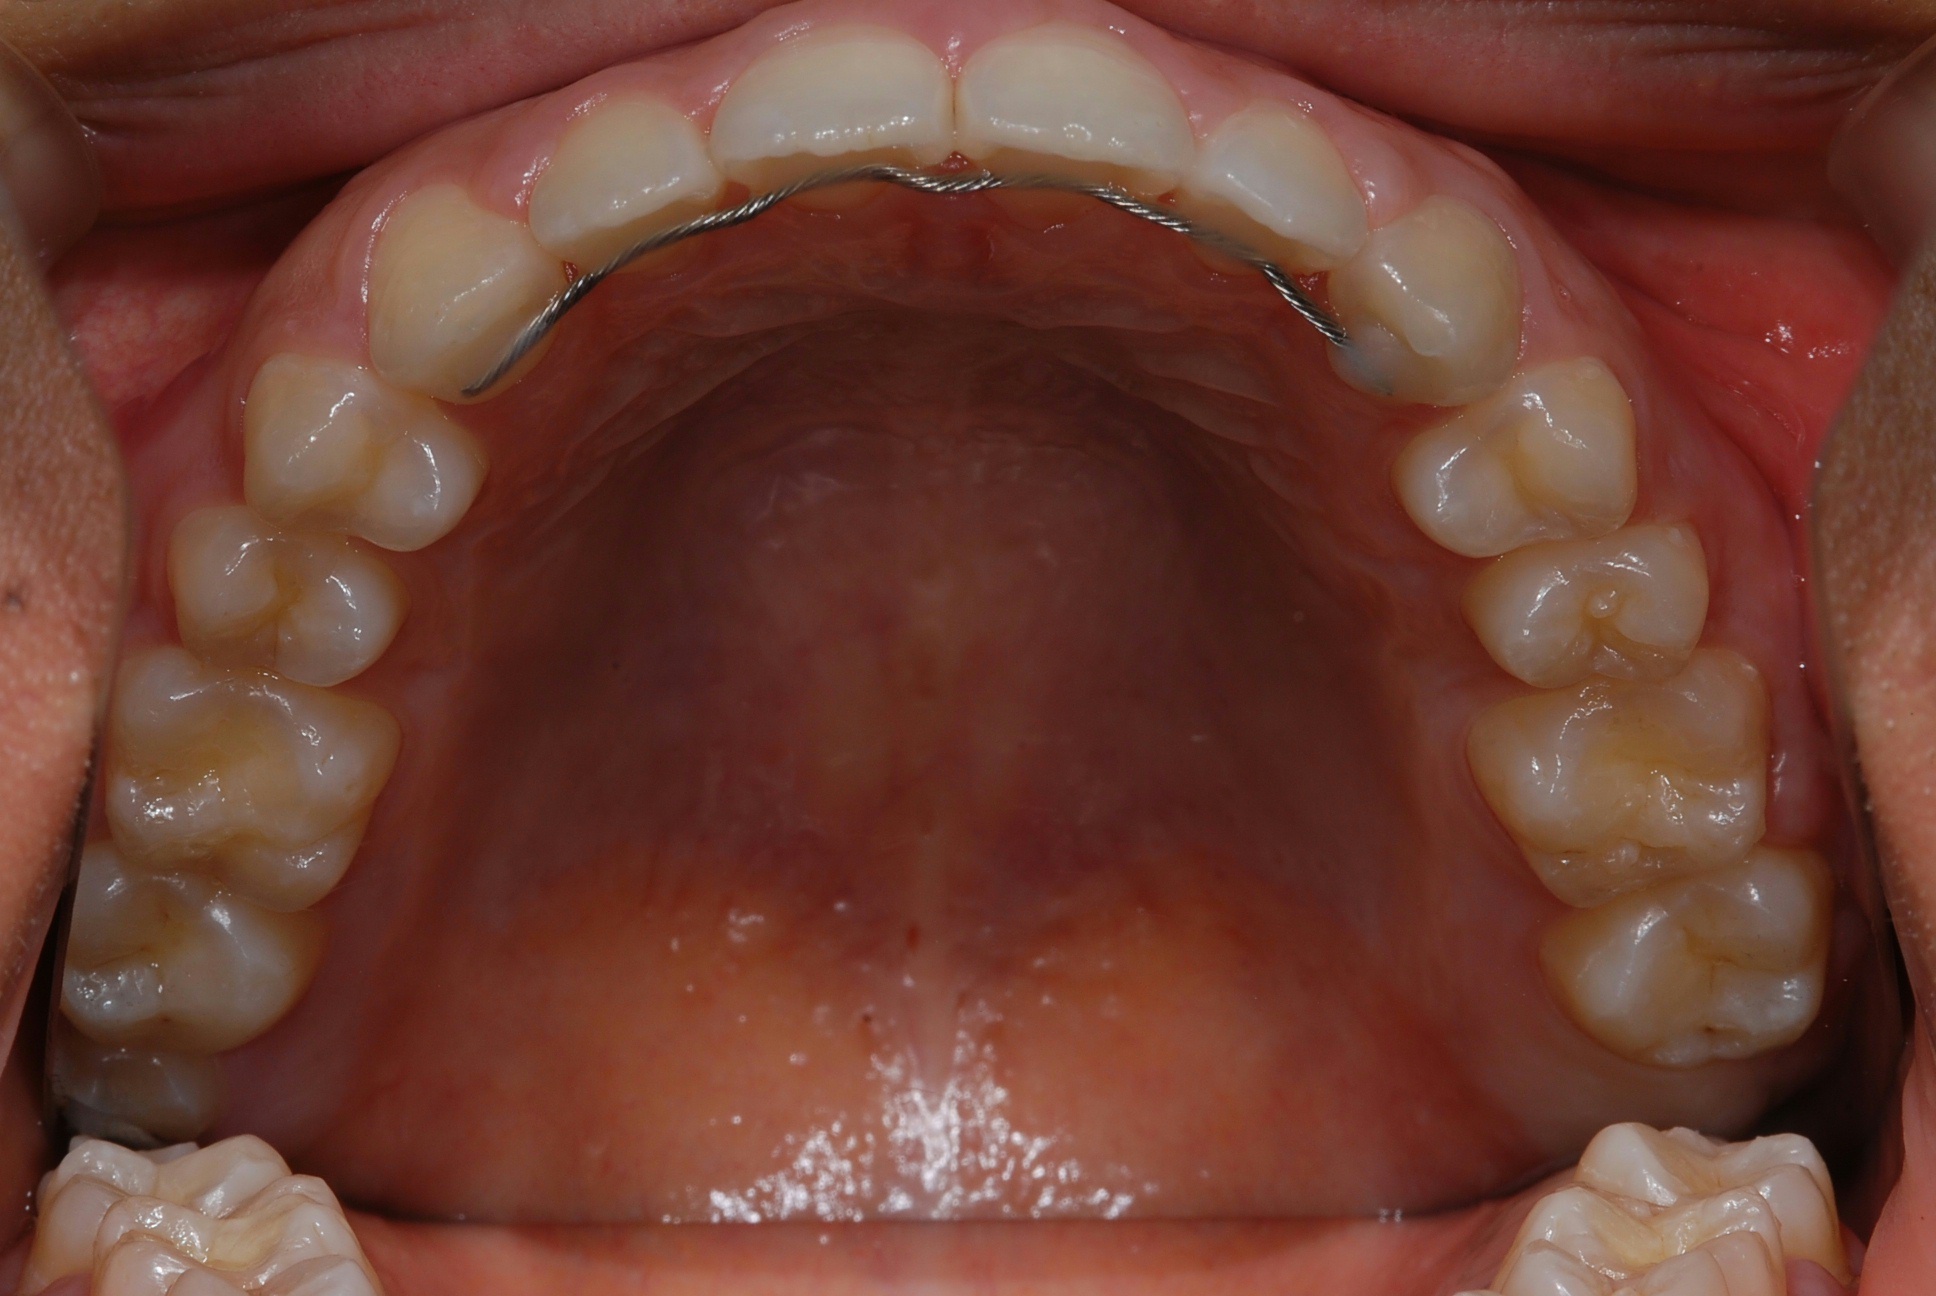

치료 후 사진입니다.